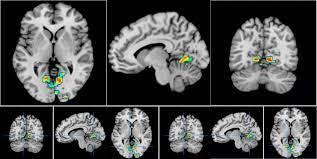

结果显示,大脑中主要参与面孔视觉处理的区域可以将「刚认识的」和「过往认识的」面孔的身份准确地解码。

而在解码过往熟识的人的身份时,研究结果表明,志愿者的大脑中有更多的共享信息,而且解码区域也不限于视觉区域。

解码过往熟识的人的身份时,在视觉系统以外的其他四个区域都有很高的解码准确率。

这四个区域包括背内侧前额叶皮层(已知它参与社会信息加工,处理他人的意图和特征);楔前叶(这个区域在处理过往熟悉的面孔时表现得更加活跃);脑岛(已知是参与情绪处理的);以及在社会认知和代表他人精神状态方面(也称为「心灵理论」)发挥重要作用的颞顶连接。

「心灵理论」区域